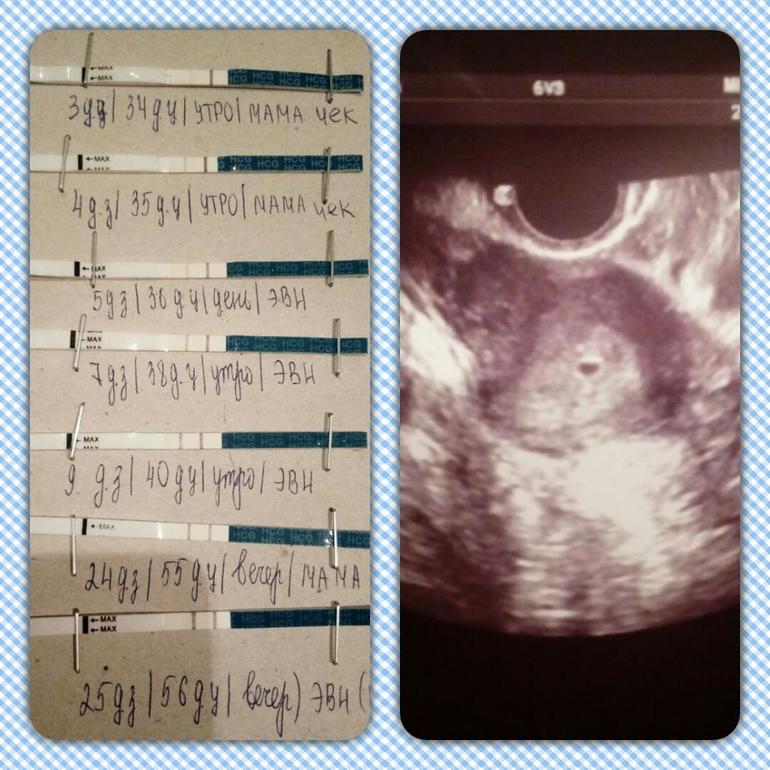

Сегодня утром сдала первый раз кровь на ХГЧ. После обеда получила результат. Он равен 7421 мЕд/мл.

Сдавала в ИНВИТРО. Если верить их расшифровке, то это 4-5 недель эмбриональной беременности. То есть от зачатия. А если по месячным, то уже 9-ая неделя. Значит О точно поздней была. Девочки, у кого какой ХГЧ был на этом сроке? Не маловат ли он у меня? Я прекрасно понимаю, что ХГЧ в динамике смотрят, но всё же.....

Сегодня утром в комоде случайно нашла тест на беременность Эвик, он просрочен аж в феврале этого года. И ради смеха я его сделала, а на нем полоски на много ярче, чем на годных тестах

По месячным будет 9 недель, но поскольку овуляция поздняя была (я так думаю), то и схожу на повторное УЗИ позже... По моим подсчётам овулька была приблизительно 10 октября, а женский календарь писал, что она должна быть 3 октября....

Так что акушерский срок сейчас 7 недель и 2 дня, а фактически думаю, что от силы недель 5.... И то в воскресенье 5 будет... Но это всё мои доводы...